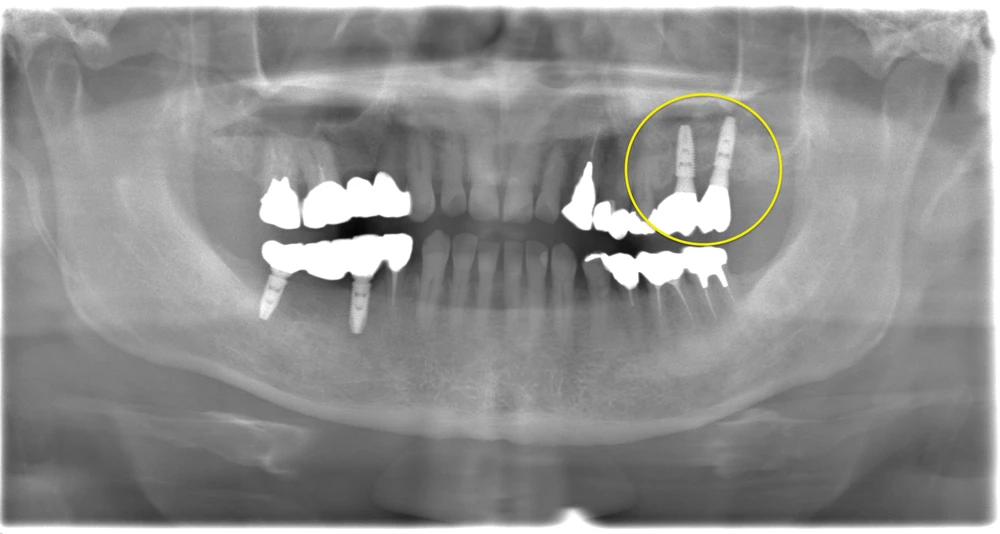

Before

After